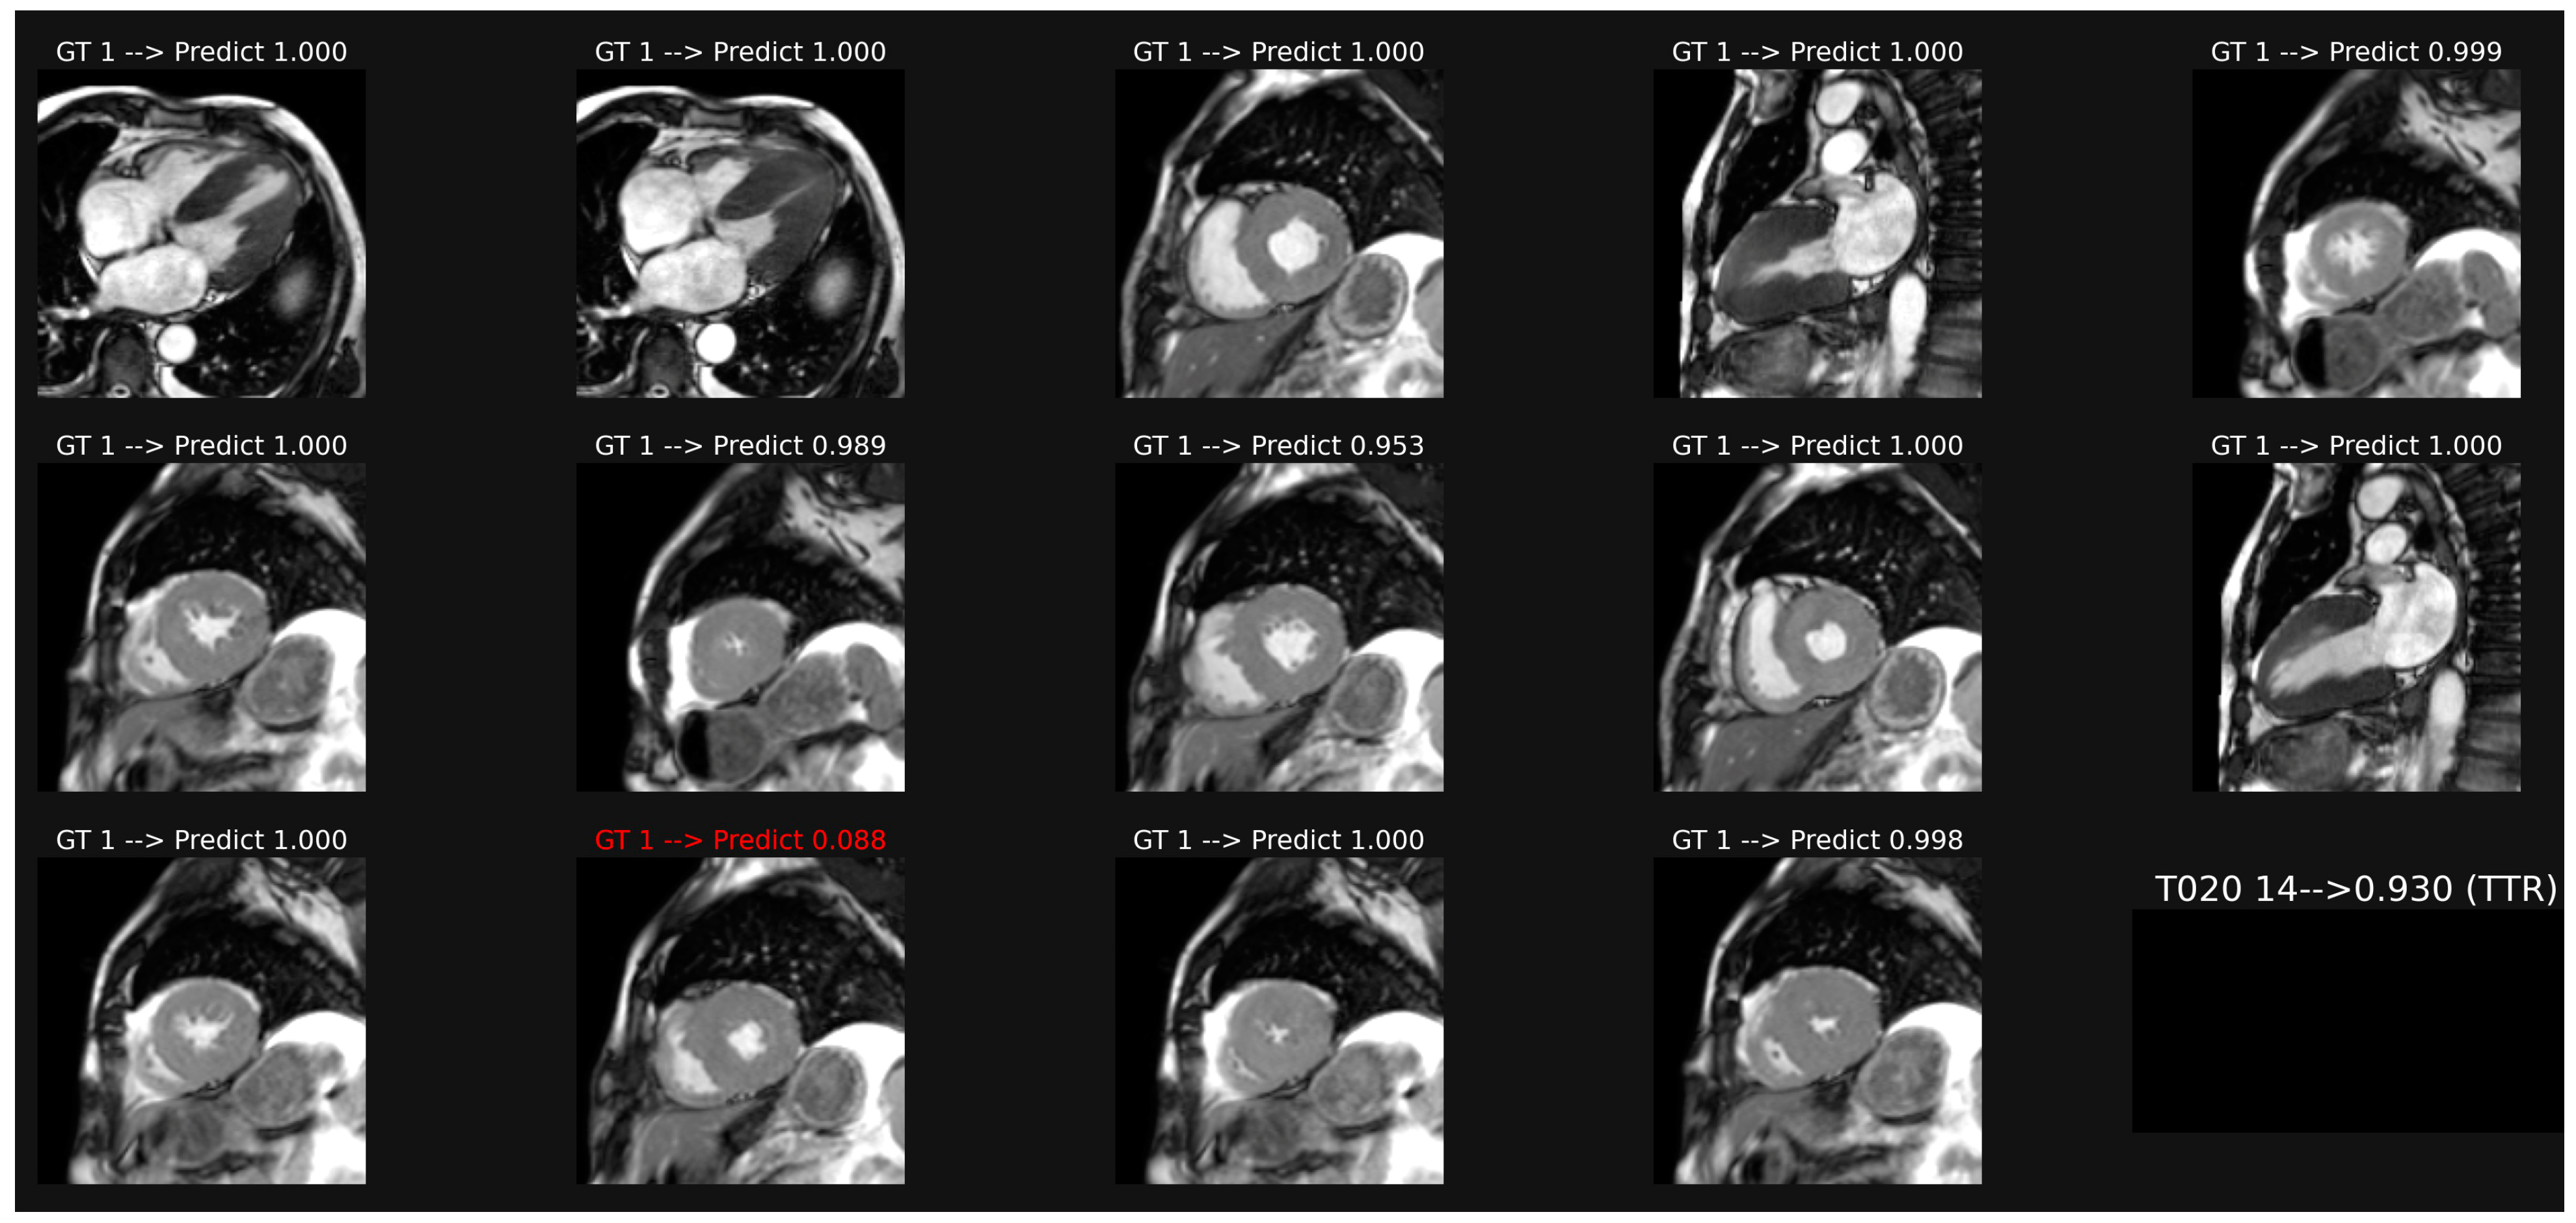

3.1. Classification of Cine-MR Images

3.5. Analysis of Saliency Maps for cineMR Images